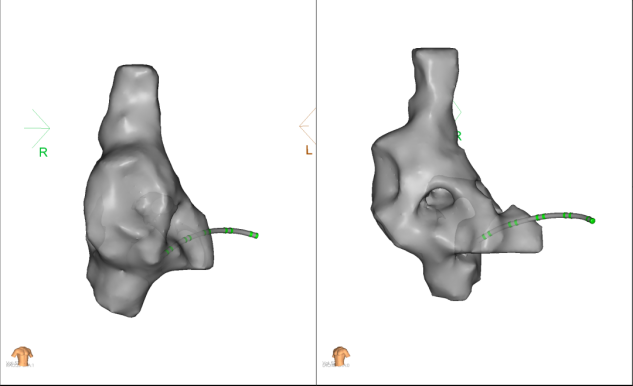

随后在三维标测系统指导下置入ICE导管及磁定位调弯十极导管并送入冠状静脉窦内。

再通过11F鞘经8.5F固定弯鞘在ICE指引下顺利完成房间隔穿刺,之后通过ICE导管在LEAD-MAPPING三维标测系统中建立左心房及肺静脉三维模型,使用PFA导管依次行肺静脉口部消融。